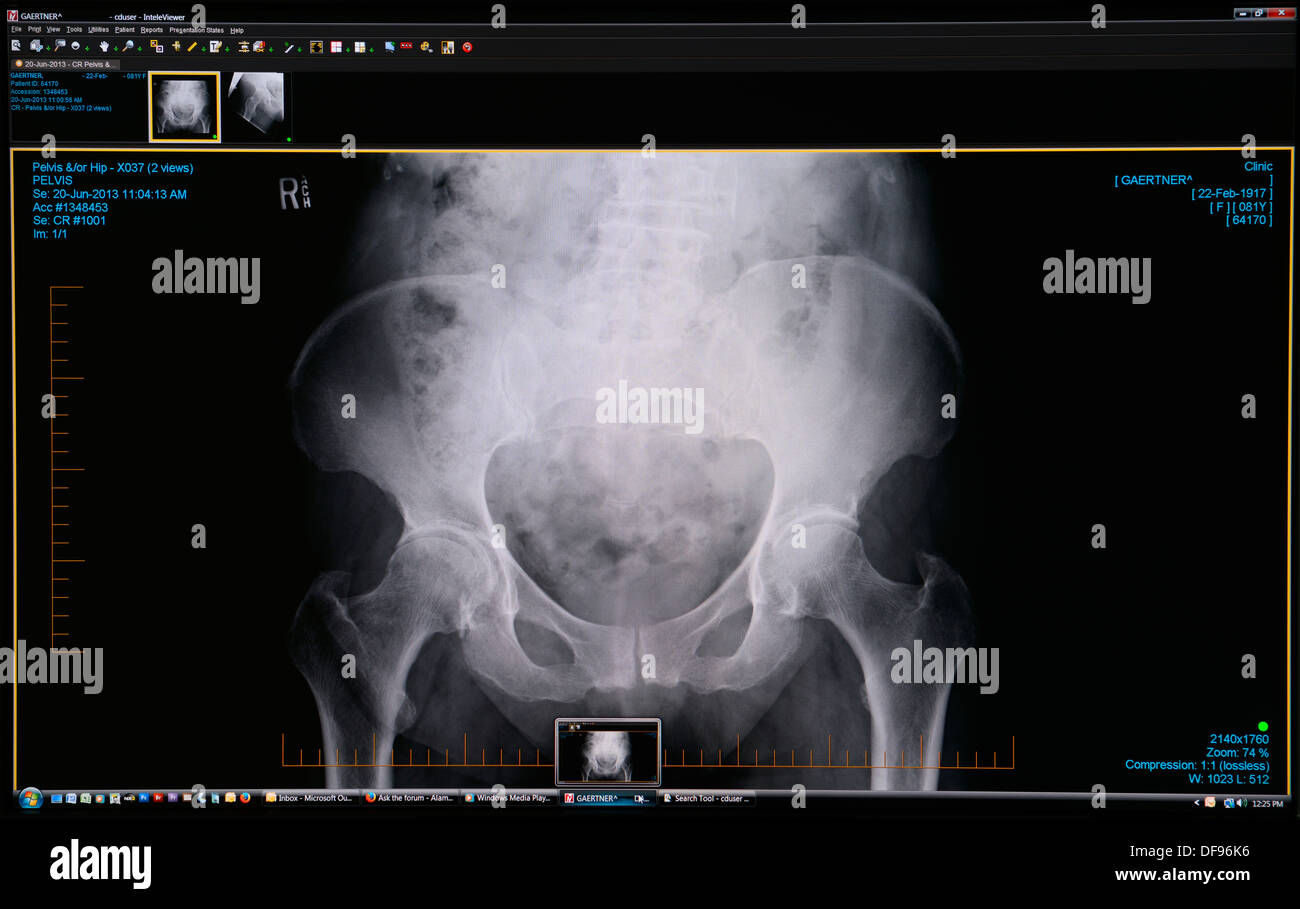

Computer screen shot of a diagnostic medical hip X-Ray scan image showing joints needing replacement surgery Stock Photohttps://www.alamy.com/image-license-details/?v=1https://www.alamy.com/computer-screen-shot-of-a-diagnostic-medical-hip-x-ray-scan-image-image61053754.html

Computer screen shot of a diagnostic medical hip X-Ray scan image showing joints needing replacement surgery Stock Photohttps://www.alamy.com/image-license-details/?v=1https://www.alamy.com/computer-screen-shot-of-a-diagnostic-medical-hip-x-ray-scan-image-image61053754.htmlRMDF96K6–Computer screen shot of a diagnostic medical hip X-Ray scan image showing joints needing replacement surgery